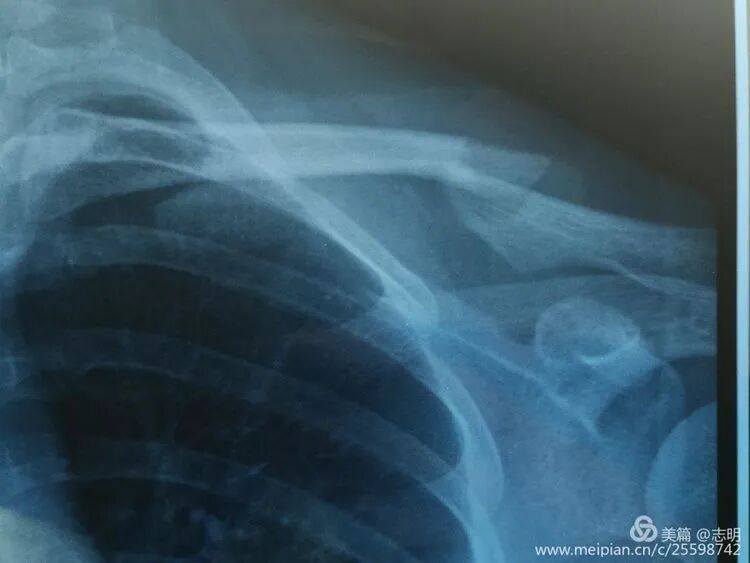

-

(X-ray showing pre-reduction fracture).

(Initial fluoroscopic view of the fracture). -

(Another pre-reduction X-ray).